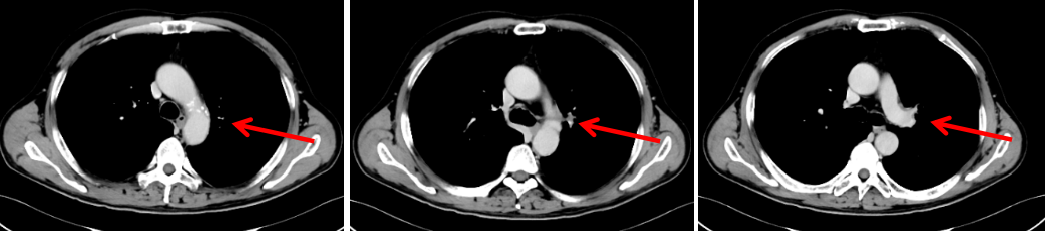

胸部CT(我院):1.左中心型肺癌并左肺门淋巴结转移;2.考虑左肺纤维灶。

图3:2020年1月30日,治疗前胸部CT

图6:2020年3月20日,联合治疗2周期后胸部CT

图8:2020年5月4日,联合治疗4周期后胸部CT

病例二总结

本例患者为“左肺上叶小细胞癌(广泛期,cT3N1M1,IV期),伴左肺门淋巴结转移、多发脑转移”,考虑予以免疫联合化疗。为明确并监测患者可能出现的毒副反应,先予以患者1周期EP方案化疗,同时予以全脑放疗1个月。患者未出现明显不良反应,予以患者加用替雷利珠单抗免疫治疗2周期,疗效评价即达到PR,治疗6周期后疗效达到CR。随访至今PFS已超过7个月,疗效持续CR,安全性良好,患者可以耐受。